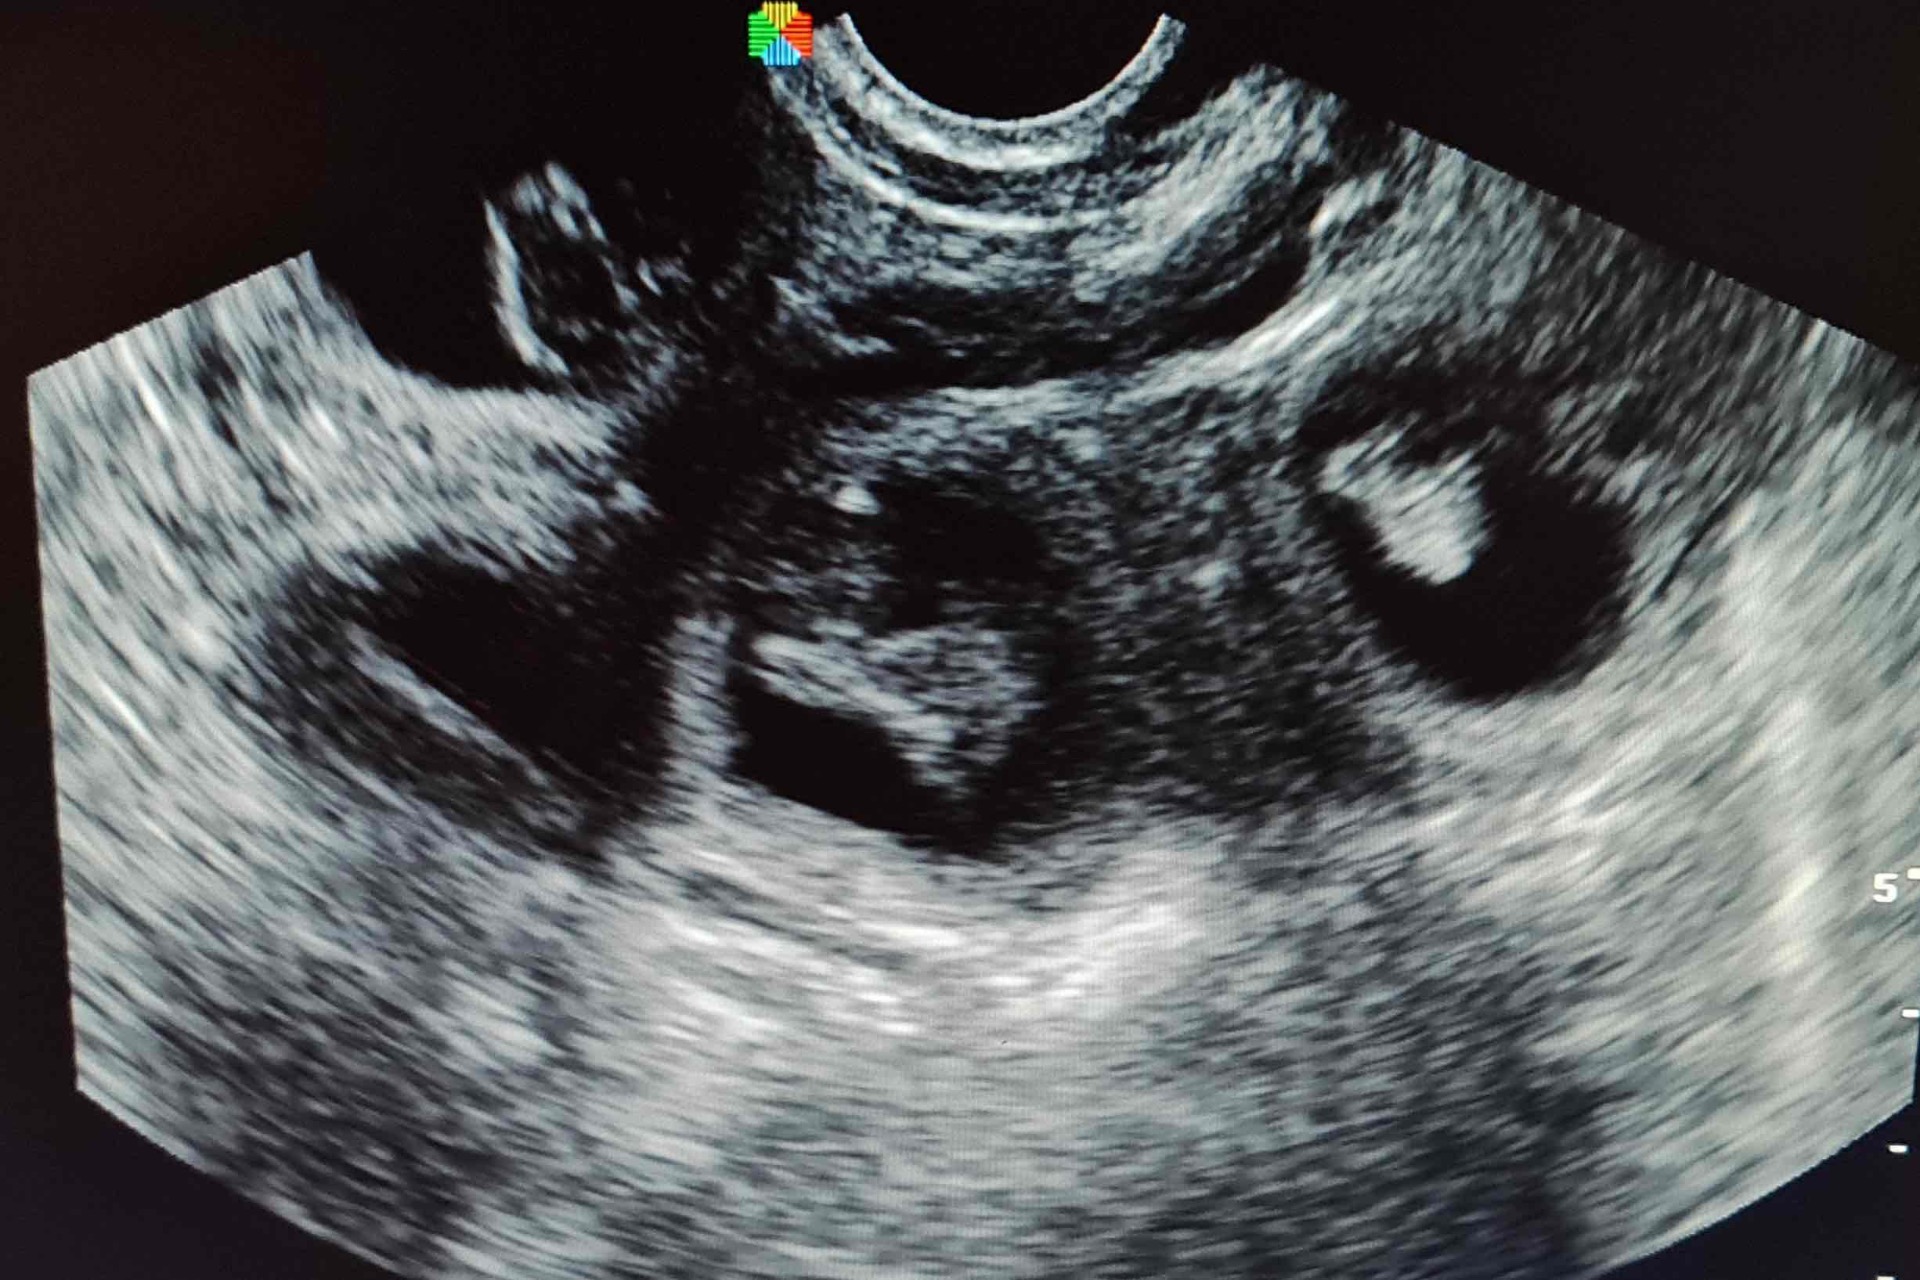

Diagnostika gravidity

Ultrasonografia: spoľahlivá od 21.–25. dňa

Relaxínový test: od 25.–30. dňa

Palpácia: medzi 24.–30. dňom (vyžaduje skúsenosť)

vyvíja sa srdce (pulzáciu možno sonograficky zachytiť už okolo 22.–25. dňa)